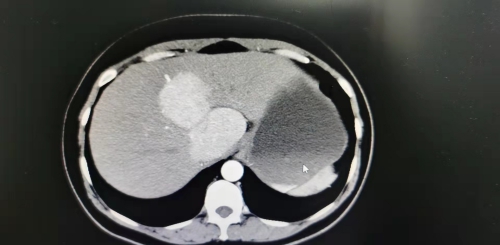

我妻子现年46岁,8月29日进行常规体检,发现肝脏生出了两个鸡蛋大的肿瘤,且长在肝内尾状叶危险部位,这种情况只有十万分之一二,且百分之九十概率是恶性肿瘤,两个肿瘤直接压迫静脉主血管,必须动手术。当时我和我爱人两腿瘫软,不知如何是好。由于这个部位血管密布,手术难度极高,很容易出现大出血或切除不干净的状况。我们开始都做好了去上海更大医院医治的打算,但8月30日黄主任和饶主任医疗诊治小组高度重视,当面耐心仔细地分析了我妻子的病情,并提出了先进全面细致的诊治方案。黄主任和饶主任说他们将亲自实施我妻子的手术,从黄主任和饶主任的谈话语气中我信服了他们医术高超,决定将我妻子的命运托付给他们。

经过一系列术前各项会诊精细准备,通过前期检查,基本定性为良性肿瘤。9月3日我妻子8点半被推进了手术室,麻醉科王少林副主任医师及各位医护人员经验丰富,让我妻子心情放松地进入了手术状态。作为患者的家属,我在等候厅看着显示屏只有焦急地等待,时间一分一秒的难熬地过去,到了十二点,显示屏依然显示我妻子还是在手术中,可见手术难度之大。直到下午两点,手术室的门打开,黄主任把我叫过去,给我看了两个鸡蛋大完整切除的肿瘤,告诉我,手术很成功,两个肿瘤完全切除,并且是按照预定计划成功实施了微创手术。听到黄主任轻松的话语,实则整个手术应该是惊心动魄,展示了整个医疗团队精湛的医术和仁者仁心。正是他们持续5个小时,中午不休,不间断的工作,终于取得了手术的圆满成功,是他们拯救了我妻子的生命,我代表我和我的妻子及我未满13岁的儿子发自内心地感恩,感恩江西省人民医院,感恩黄长文主任手术团队王少林主任的麻醉团队和参与手术的护理人员的仁者善心。